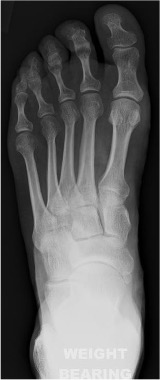

Dorsoplantar view foot (DP)

Radiographic technique

Taken either weightbearing or non-weightbearing with the X-ray beam angled 10° towards the heel (so that it is perpendicular to the metatarsals) and directed to the base of the third metatarsal.

Anatomical review areas

- General-purpose view shows the majority of the foot from the midtarsal area distally

- The neck of the talus, distal calcaneus, tarsus, metatarsals, metatarsophalangeal joints and phalanges clearly seen

- Calcaneo-cuboid and talo-navicular joints making up the midtarsal (Chopart) joint

- Tarso-metatarsal (Lisfranc) joint

- Sesamoid bones seen through the first metatarsal head

- Bodies of talus and calcaneum occluded by superimposition of the distal tibia and fibula